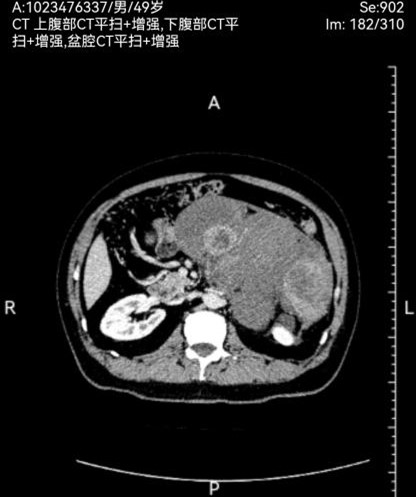

此次两名患者均因“腹部胀痛、包块及进食受限”入院,经增强CT三维重建及磁共振等检查,确诊为腹膜后巨大肿瘤。一例左侧腹膜后肿瘤,长径达30cm,重约4.8kg,紧贴腹主动脉及腹腔干,侵犯脾动脉根部及胰体尾、脾门、右肾及右肾上腺,与结肠系膜粘连紧密,挤压胃肠道引发不全梗阻;另一例右侧腹膜后肿瘤,长径40cm,重约3.2kg,侵犯结肠系膜根部血管,血供丰富,同时挤压肝门及十二指肠,存在右肾蒂损伤风险。